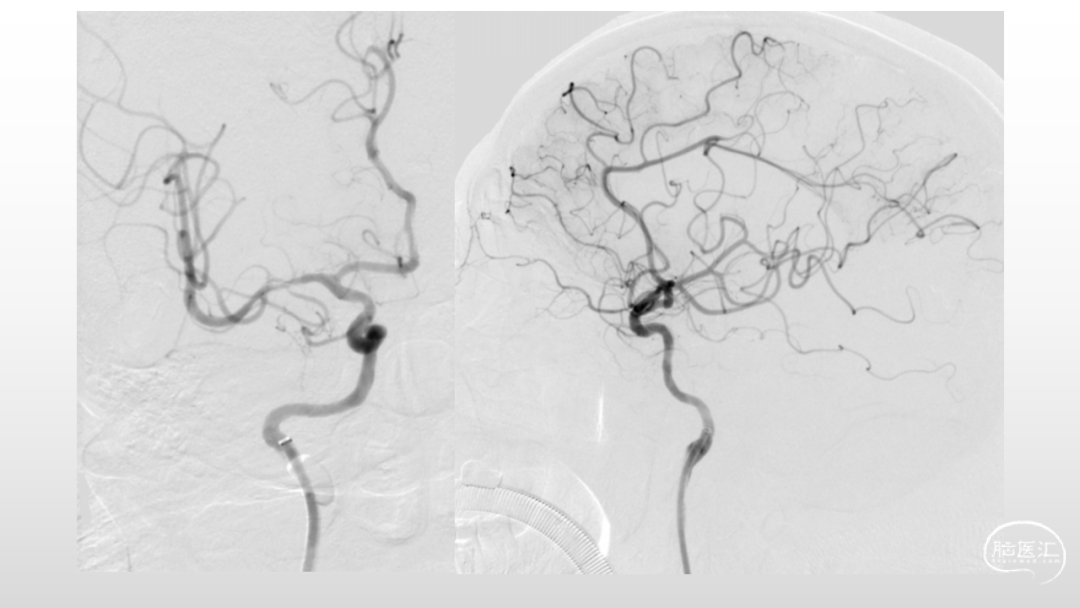

取之有道·第54期|李子付:Flowgate2取栓应用